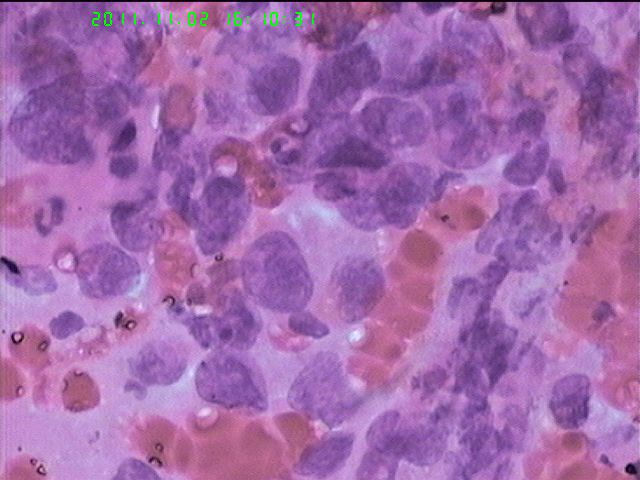

男65岁支气管刷片

查见恶性肿瘤细胞,首先考虑为大细胞性未分化癌。

非小细胞肺癌,倾向为鳞癌可能性大。

非小细胞癌。

非小细胞癌

打癌没有问题,鳞腺的区分有时候非常困难。非小细胞癌。确实要分的话,打腺癌。好像癌有腺样趋势。

非小细胞癌  倾向于腺癌

活检:鳞癌。

鳞癌细胞